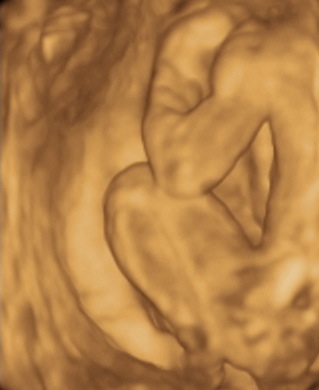

A 3D-s babafotok meg mindig lenyugoznek, nem birok betelni veluk. SZomoruan olvasom, hogy mennyi aprobb-nagyobb kellemetlensegetek van, de szerintem mindenki nagyon szuperul halad, ugyesek vagytok...le a kalappal foleg a dolgozok, vagy mar babasok elott! majd most teszek fel kepeket es is Azzurrarol, bar mar tobb, mint 5 hete keszultek, de ujabbak mar nem lesznek, es mivel kimaradtam abban az idoszakban, most potolom. Az tuti, hogy ezentul mindenkinek javasolni fogom a 4D-t ilyen koran is (22+1 hetesen voltunk), mert bar csimota ducibb volt az atlagnal es mar akkor volt rajta jo adagnyi izom (ez is a napi 1 l tej

), de egy sovanyabb baba is csodaszep szerintem...mindent el lehet mondani, csak azt nem, hogy csontkollekciok lennenek. Osszessegeben ugy nez ki, hogy ram hasonlit, de a szemoldokcsontja es a szaja az egy az egyben a parome...szerencsere...neki az sokkal szebb...remelem, haj-ugyben is ra ut majd